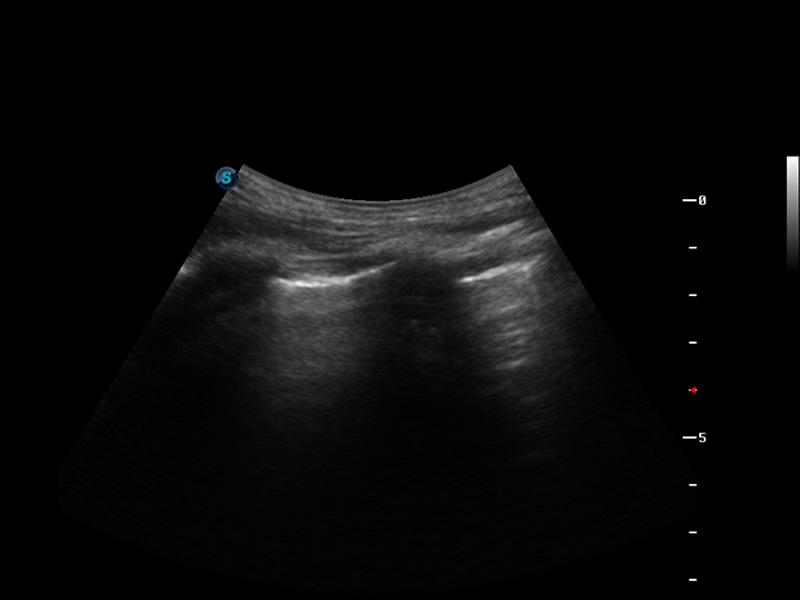

S9便携式彩色多普勒超声诊断仪是美狮贵宾会官网研发的高端便携彩超设备,外观设计新颖、产品性能卓越。S9在便携超声领域采用了突破传统的触摸屏交互设计,并以先进的软件硬件技术和设计理念,为您带来清晰的图像质量、稳定的工作性能和便捷的操作体验。

脉冲反相谐波成像